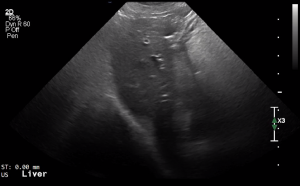

SIMON Ultrasound Database

This ultrasound database is a free resource for students and doctors!

Our collection includes videos of dogs, cats, horses, cows, humans, and many other species!

–Canine and Feline abdominal ultrasound videos were generously provided by the Cummings School of Veterinary Medicine at Tufts University.